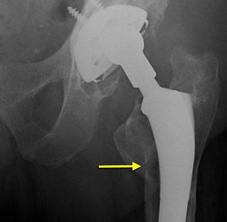

Osteolysis is a problem that causes the bone surrounding the implant to seemingly ‘melt away’. The weakening of bone around the hip replacement is seen on x-rays, and looks as though there are holes in the bone around the joint replacement. Because of the weakened bone, the hip replacement become loose, and begins to wobble within the bone. Patients experience symptoms of pain and limitations in motion of the hip. The technical name for this weakening of bone is called osteolysis.